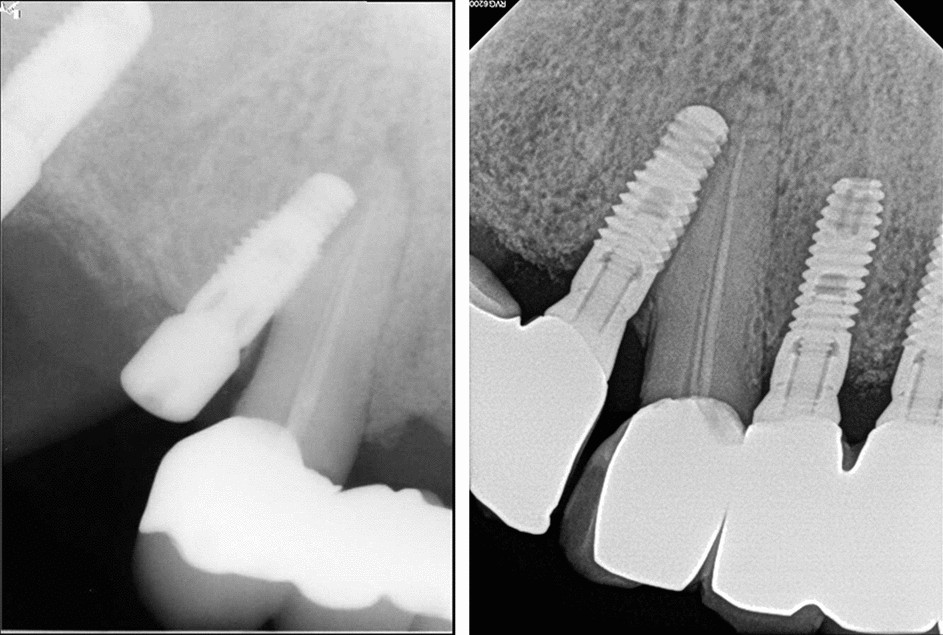

Volunteering for a clinical trial is another possible avenue to get free dental implants for a tiny group of low-income adults. Dental Implants Clinical Trial NCT03225495 - Interventional The main target of the study is to compare ultra-narrow diameter implants 275 mm without bone regeneration versus standard. Visiting your Community Health Center 3.

Long Term Clinical Result Of Implant Induced Injury On The Adjacent Tooth Scientific Reports